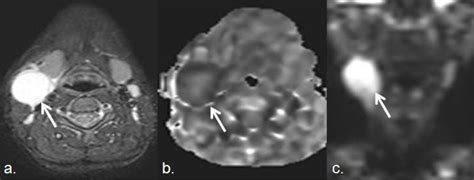

• Imaging Studies: Imaging tests such as X-rays, CT scans, or MRIs may be used to visualize the lymph nodes and surrounding tissues.